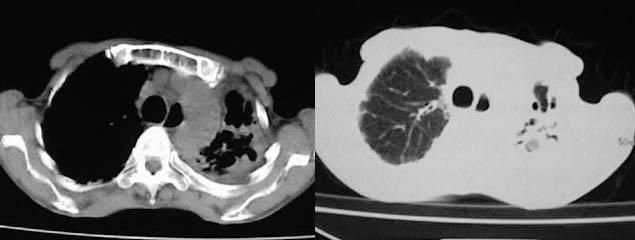

以下是引用有风的日子在2008-5-2 12:13:00的发言:[br][emb10][br][br]肺ca?有病理支持吗?[br][br]我看更象是肺tb并支扩、间质性肺炎。最好拿个病理结果来,不然这点影像资料诊断肺ca是难以服人的![br][br]至于主动脉瘤的诊断问题,国外认为≥4.0cm就可诊断了,国内对此诊断标准更为严格。患者升主动脉明显增粗,即>4cm。你诊断个升主动脉扩张并不为过!

以下是引用zjzjr在2008-5-2 14:39:00的发言:[br]支持双侧继发型肺结核,左侧胸膜肥厚,慢性支气管炎伴间质纤维化.